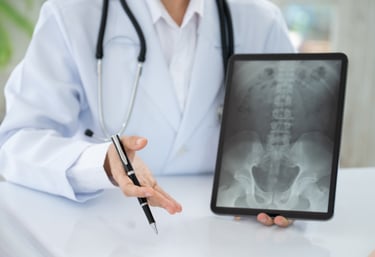

En trygg väg till diagnos genom bilddiagnostik

Som legitimerad kiropraktor vägleder jag dig från klinisk misstanke till tolkning av resultat.

Som en del av din utredning på Kroppia gör vi en noggrann klinisk bedömning av om bilddiagnostik är nödvändig för att fastställa rätt diagnos eller säkerställa att behandling kan ske tryggt.

Vi börjar alltid med en grundlig klinisk funktionsanalys. Bilddiagnostik används som ett precisionsverktyg när vi behöver bekräfta fynd eller utesluta bakomliggande orsaker som inte syns vid en manuell undersökning.

Vi går igenom dina röntgen- eller MR-svar tillsammans. Det viktigaste är hur bilderna korrelerar med din biomekaniska status, så att vi kan utforma en träffsäker behandlingsplan.

Tolkning & Åtgärd